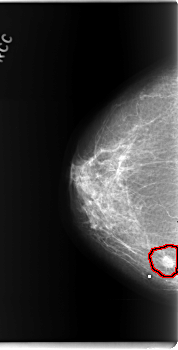

C_0202_1.RIGHT_CC

RIGHT_CC LINES 5936 PIXELS_PER_LINE 3024 BITS_PER_PIXEL 12 RESOLUTION 50 OVERLAY

FILE: C_0202_1.RIGHT_CC.OVERLAY

TOTAL_ABNORMALITIES 1

ABNORMALITY 1

LESION_TYPE MASS SHAPE ROUND MARGINS SPICULATED

ASSESSMENT 5

SUBTLETY 5

PATHOLOGY MALIGNANT

TOTAL_OUTLINES 1

BOUNDARY